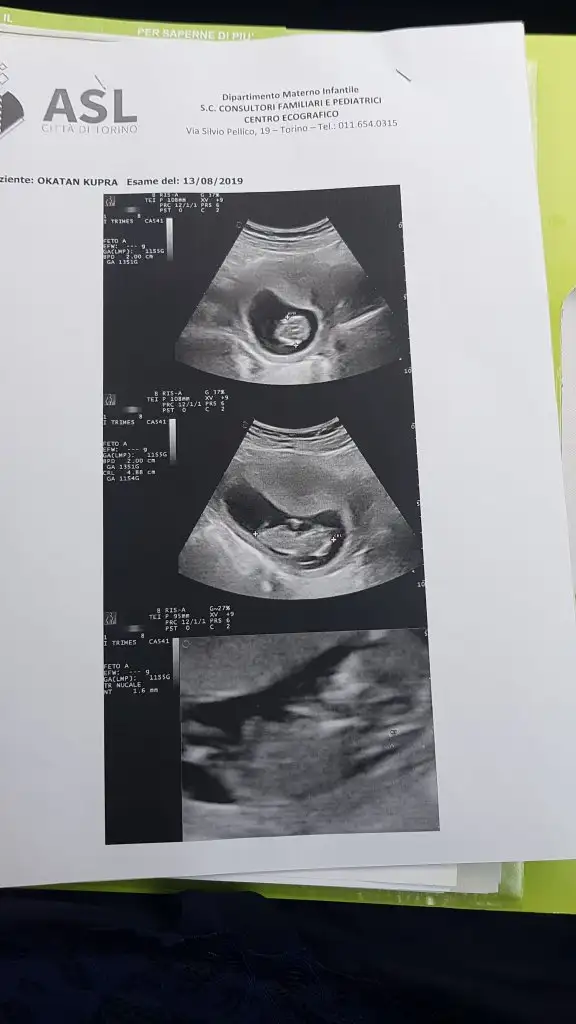

Banada bakarmsnDaha net bir goruntusu olsaydi nubuna bakarak yorum yapabilirdim ama biraz bulanik net degil foto.hayirlisi olsun saglikli olsun

Daha net bir goruntusu olsaydi nubuna bakarak yorum yapabilirdim ama biraz bulanik net degil foto.hayirlisi olsun saglikli olsun

Bakarmsn banadaDaha net yokmu sanki foto bulanik cozemedim.birsey soylemekde istemiyorum yaniltici olabilir nubu gorunuyor ama net degil